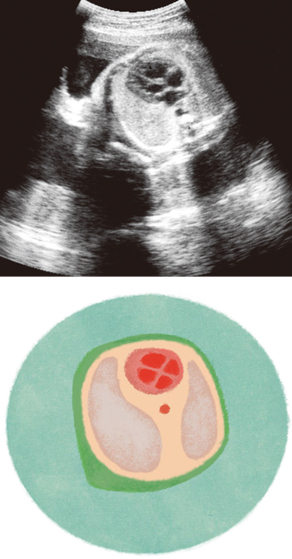

妊娠29週ころの超音波写真

心臓の弁や心拍数なども確認されます

赤ちゃんの胸あたりの断面で、心臓の中に左右の心室と心房が見えます。手前にあるのは、左右の肺。心臓の各部屋の大きさ、弁の動き、心拍数なども超音波でチェックします。